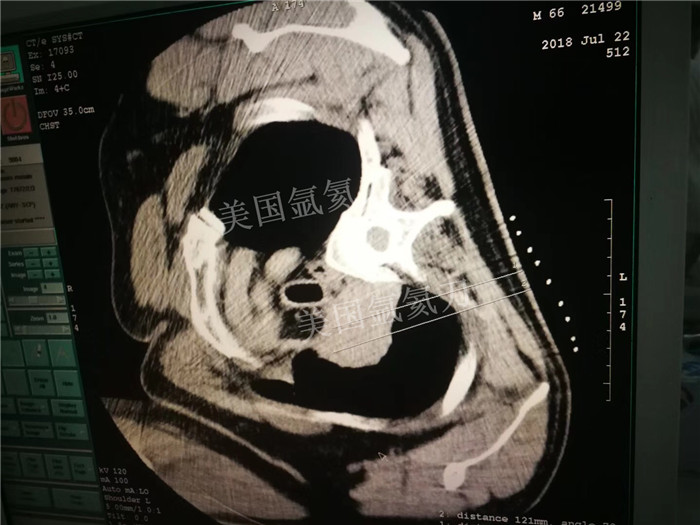

上一篇:中美国际肿瘤医院氩氦刀冷冻消融治疗子宫颈癌左髂骨内侧转移病灶

下一篇:LUS引导下氩氦刀冷冻治疗胰腺癌的初步研究